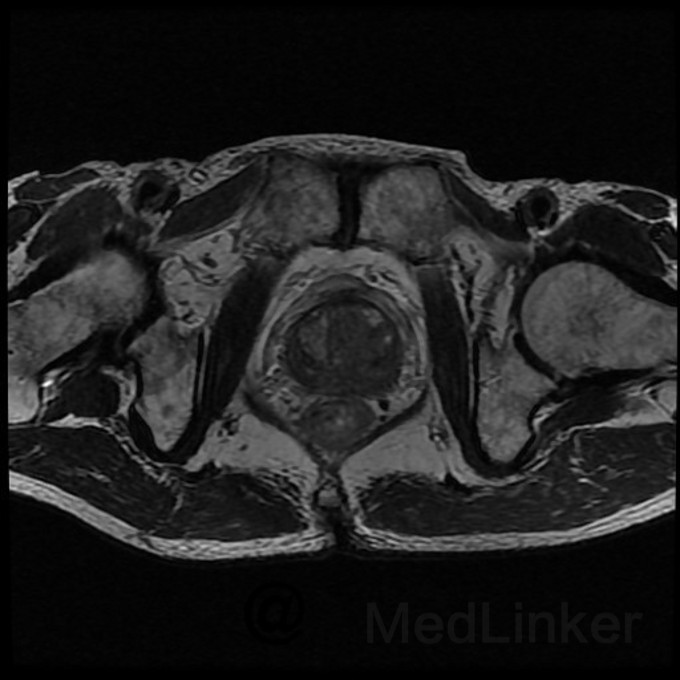

我们医院磁共振诊断前列腺疾病,好多序列,除了T2WI,还有DWI,T1WI,MRS等,到底哪个最准确,还是只要T2WI序列是低信号结节就能够诊断?附图就是一个前列腺T2WI序列,能看到低信号是不是就可以诊断是前列腺癌?